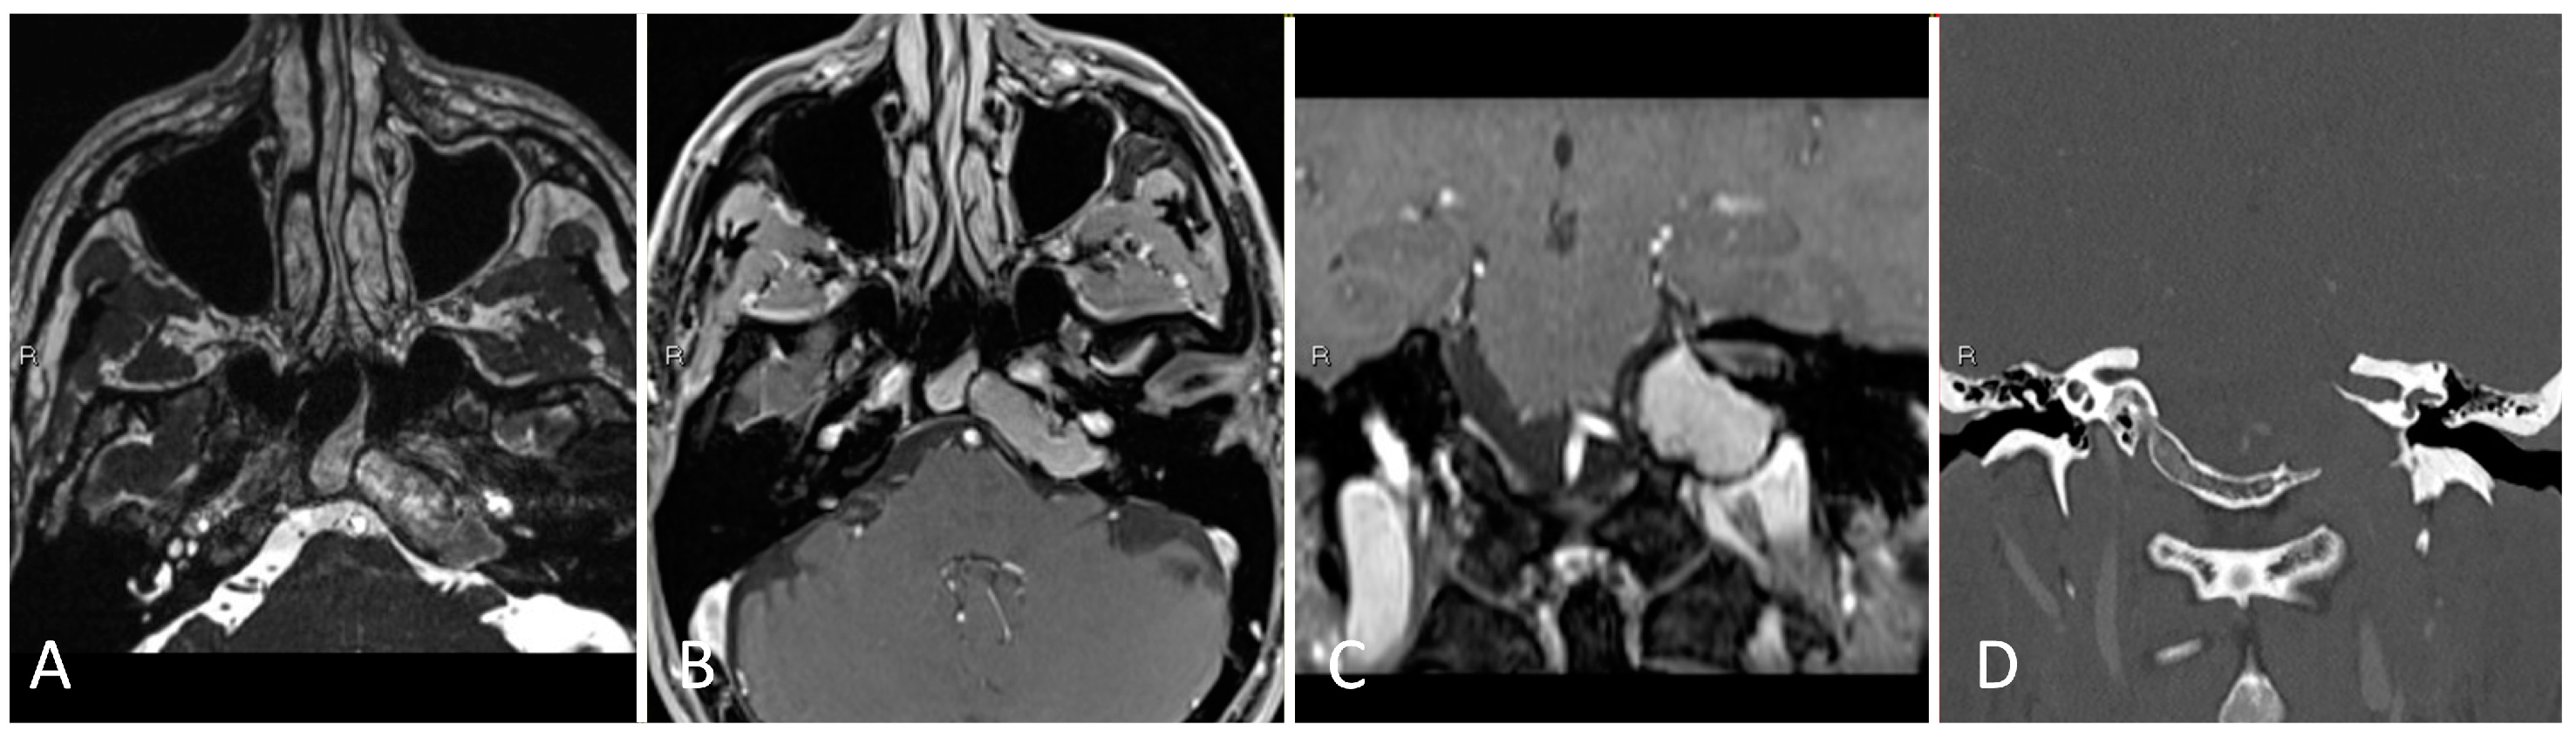

3.2.2. Illustrative Case

3.2.3. Practical Pearls

- The goals of surgical resection for metastatic lesions to the orbit are to obtain decompression of the optic apparatus and to obtain a diagnosis.

- The periorbita should be opened parallel to the medial rectus muscle to minimize inadvertent injury.

- In the medial endonasal approach, the two corridors include between the superior oblique and medial rectus muscles, as well as between the medial rectus and the inferior rectus muscles.